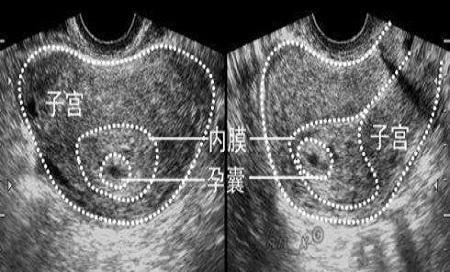

孕妈不放心的话,可以通过B超在宫腔内看到孕囊,随着胚胎不断成长,孕囊内会形成胎芽、胎心,如果孕妈在医院检查时,看得到孕囊,胎心和胎芽,就可以确认为宫内妊娠。

孕妈自己不会看拍出来的片子,可以对照下面的几项孕囊特点来看一下:

孕囊正常的特点:

- 孕囊的位置可以位于子宫的上部、中部、宫底,也可以位于前壁和后壁,都是属于正常形态,孕妈不必太担心;

- 孕囊的形状为圆形和椭圆形,看上去清晰可见,就是正常的;

- 月经期比较规律的女性,停经35天之后,就可以在宫腔内看到孕囊。

- 在怀孕6周时孕囊直径约2厘米,怀孕10周时约5厘米。